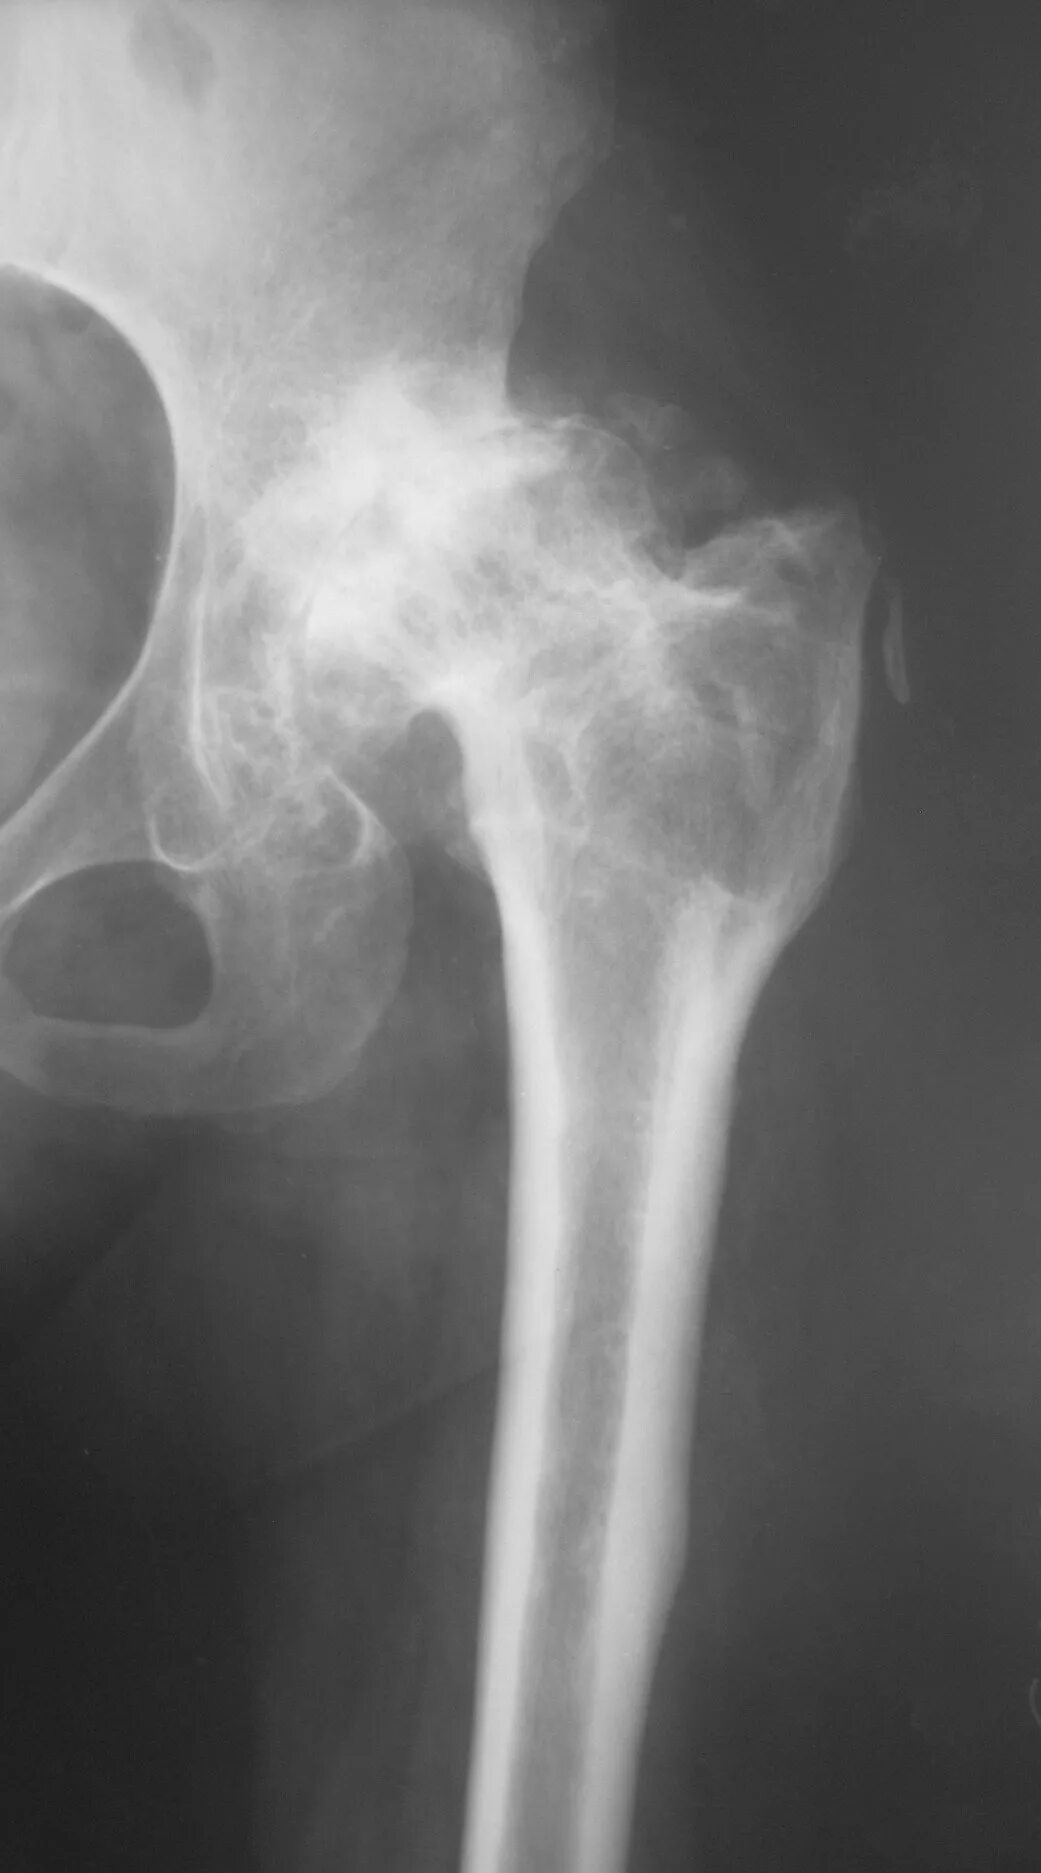

Коксартроз тазобедренного 3 степени лечение без операции